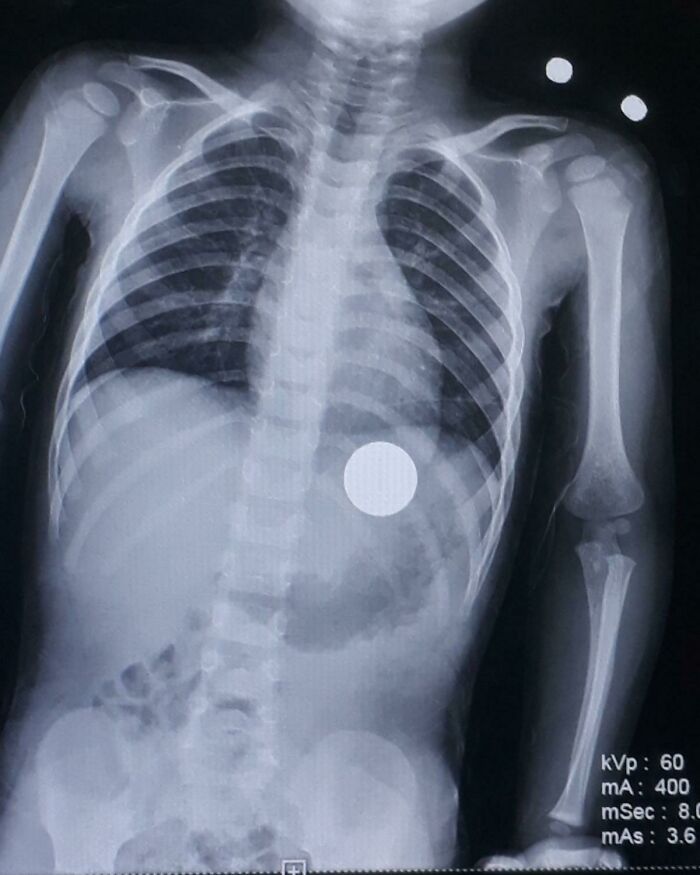

lilpastababy:

A kid came in for a cough at the urgent care I work at and they did a chest X-ray and discovered that he had this. Everyone was freaking out lol

Image source: giraffiesays, reddit